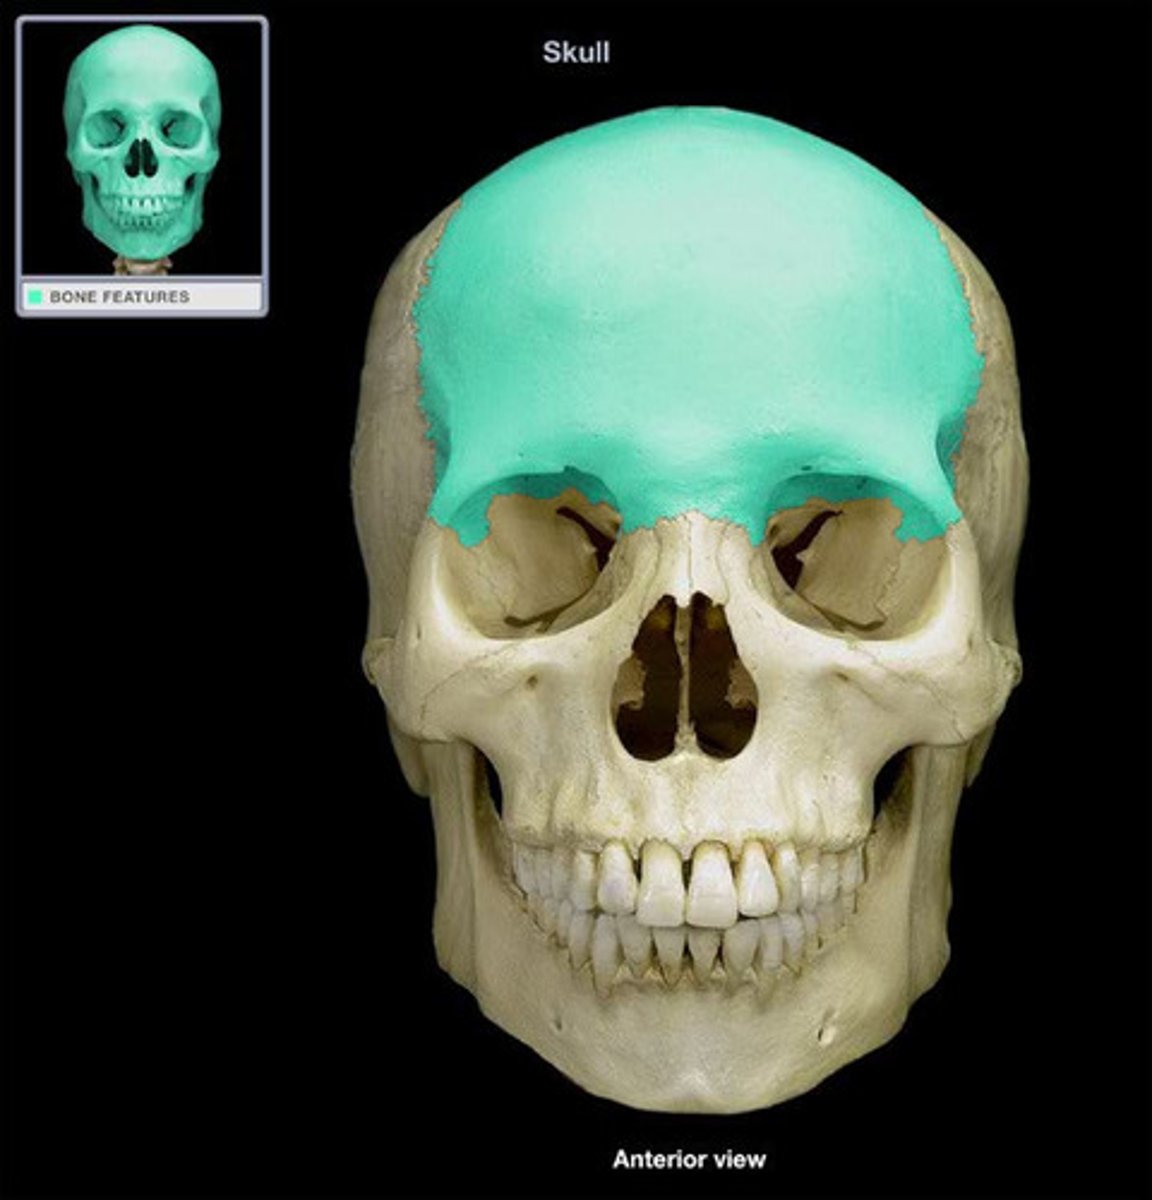

frontal bone

frontal bone